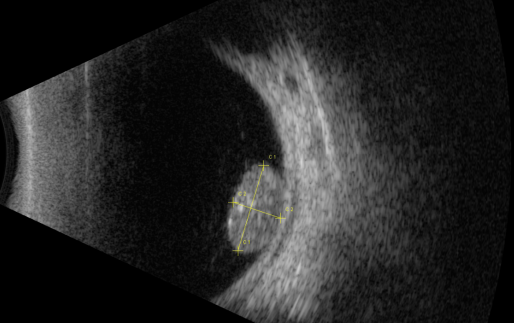

視網(wǎng)膜母細(xì)胞瘤的分類和治療

【文章導(dǎo)讀】視網(wǎng)膜母細(xì)胞瘤是嬰幼兒常見(jiàn)的眼內(nèi)惡性腫瘤,可危害患者的視力、眼球和生命。其惡性程度高,多發(fā)于兒童,尤其是3歲以下的兒童,常表現(xiàn)為白瞳癥,可侵及單眼或雙眼。 視網(wǎng)膜母

視網(wǎng)膜母細(xì)胞瘤是嬰幼兒常見(jiàn)的眼內(nèi)惡性腫瘤,可危害患者的視力、眼球和生命。其惡性程度高,多發(fā)于兒童,尤其是3歲以下的兒童,常表現(xiàn)為白瞳癥,可侵及單眼或雙眼。

視網(wǎng)膜母細(xì)胞瘤分類

視網(wǎng)膜母細(xì)胞瘤的分類

根據(jù)腫瘤的表現(xiàn)和發(fā)展過(guò)程可分為眼內(nèi)期、青光眼期、眼外期和全身轉(zhuǎn)移期。